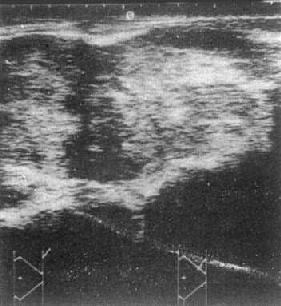

1.肾癌 USG可见肾增大、形态异常,肿瘤呈实质性暗区,其内可有细小、散在、分布均匀的光点,肿瘤侧壁出现边界不清的低回声带,肿瘤内出血坏死液化则出现液性暗区。肾盂、肾盏因受肿块推压,致其光点移位,甚至消失(图4-4-5)。血管内瘤栓形成散在或稀疏的血管内回声;肾门淋巴结增大则呈类圆实质性低回声区环绕肾蒂主动脉肾动脉的连接部;主动脉旁淋巴结增大,使大血管轮廓不清,或于腹膜后中线部出现实质性肿块,这些对肾癌的分期十分重要。肾癌术后USG检查是肿瘤复发及局部淋巴结转移的有效诊断方法。

左肾癌

图4-4-5 左肾癌

左肾大部被混杂回声肿物占据,

内部回声不均,边界不清